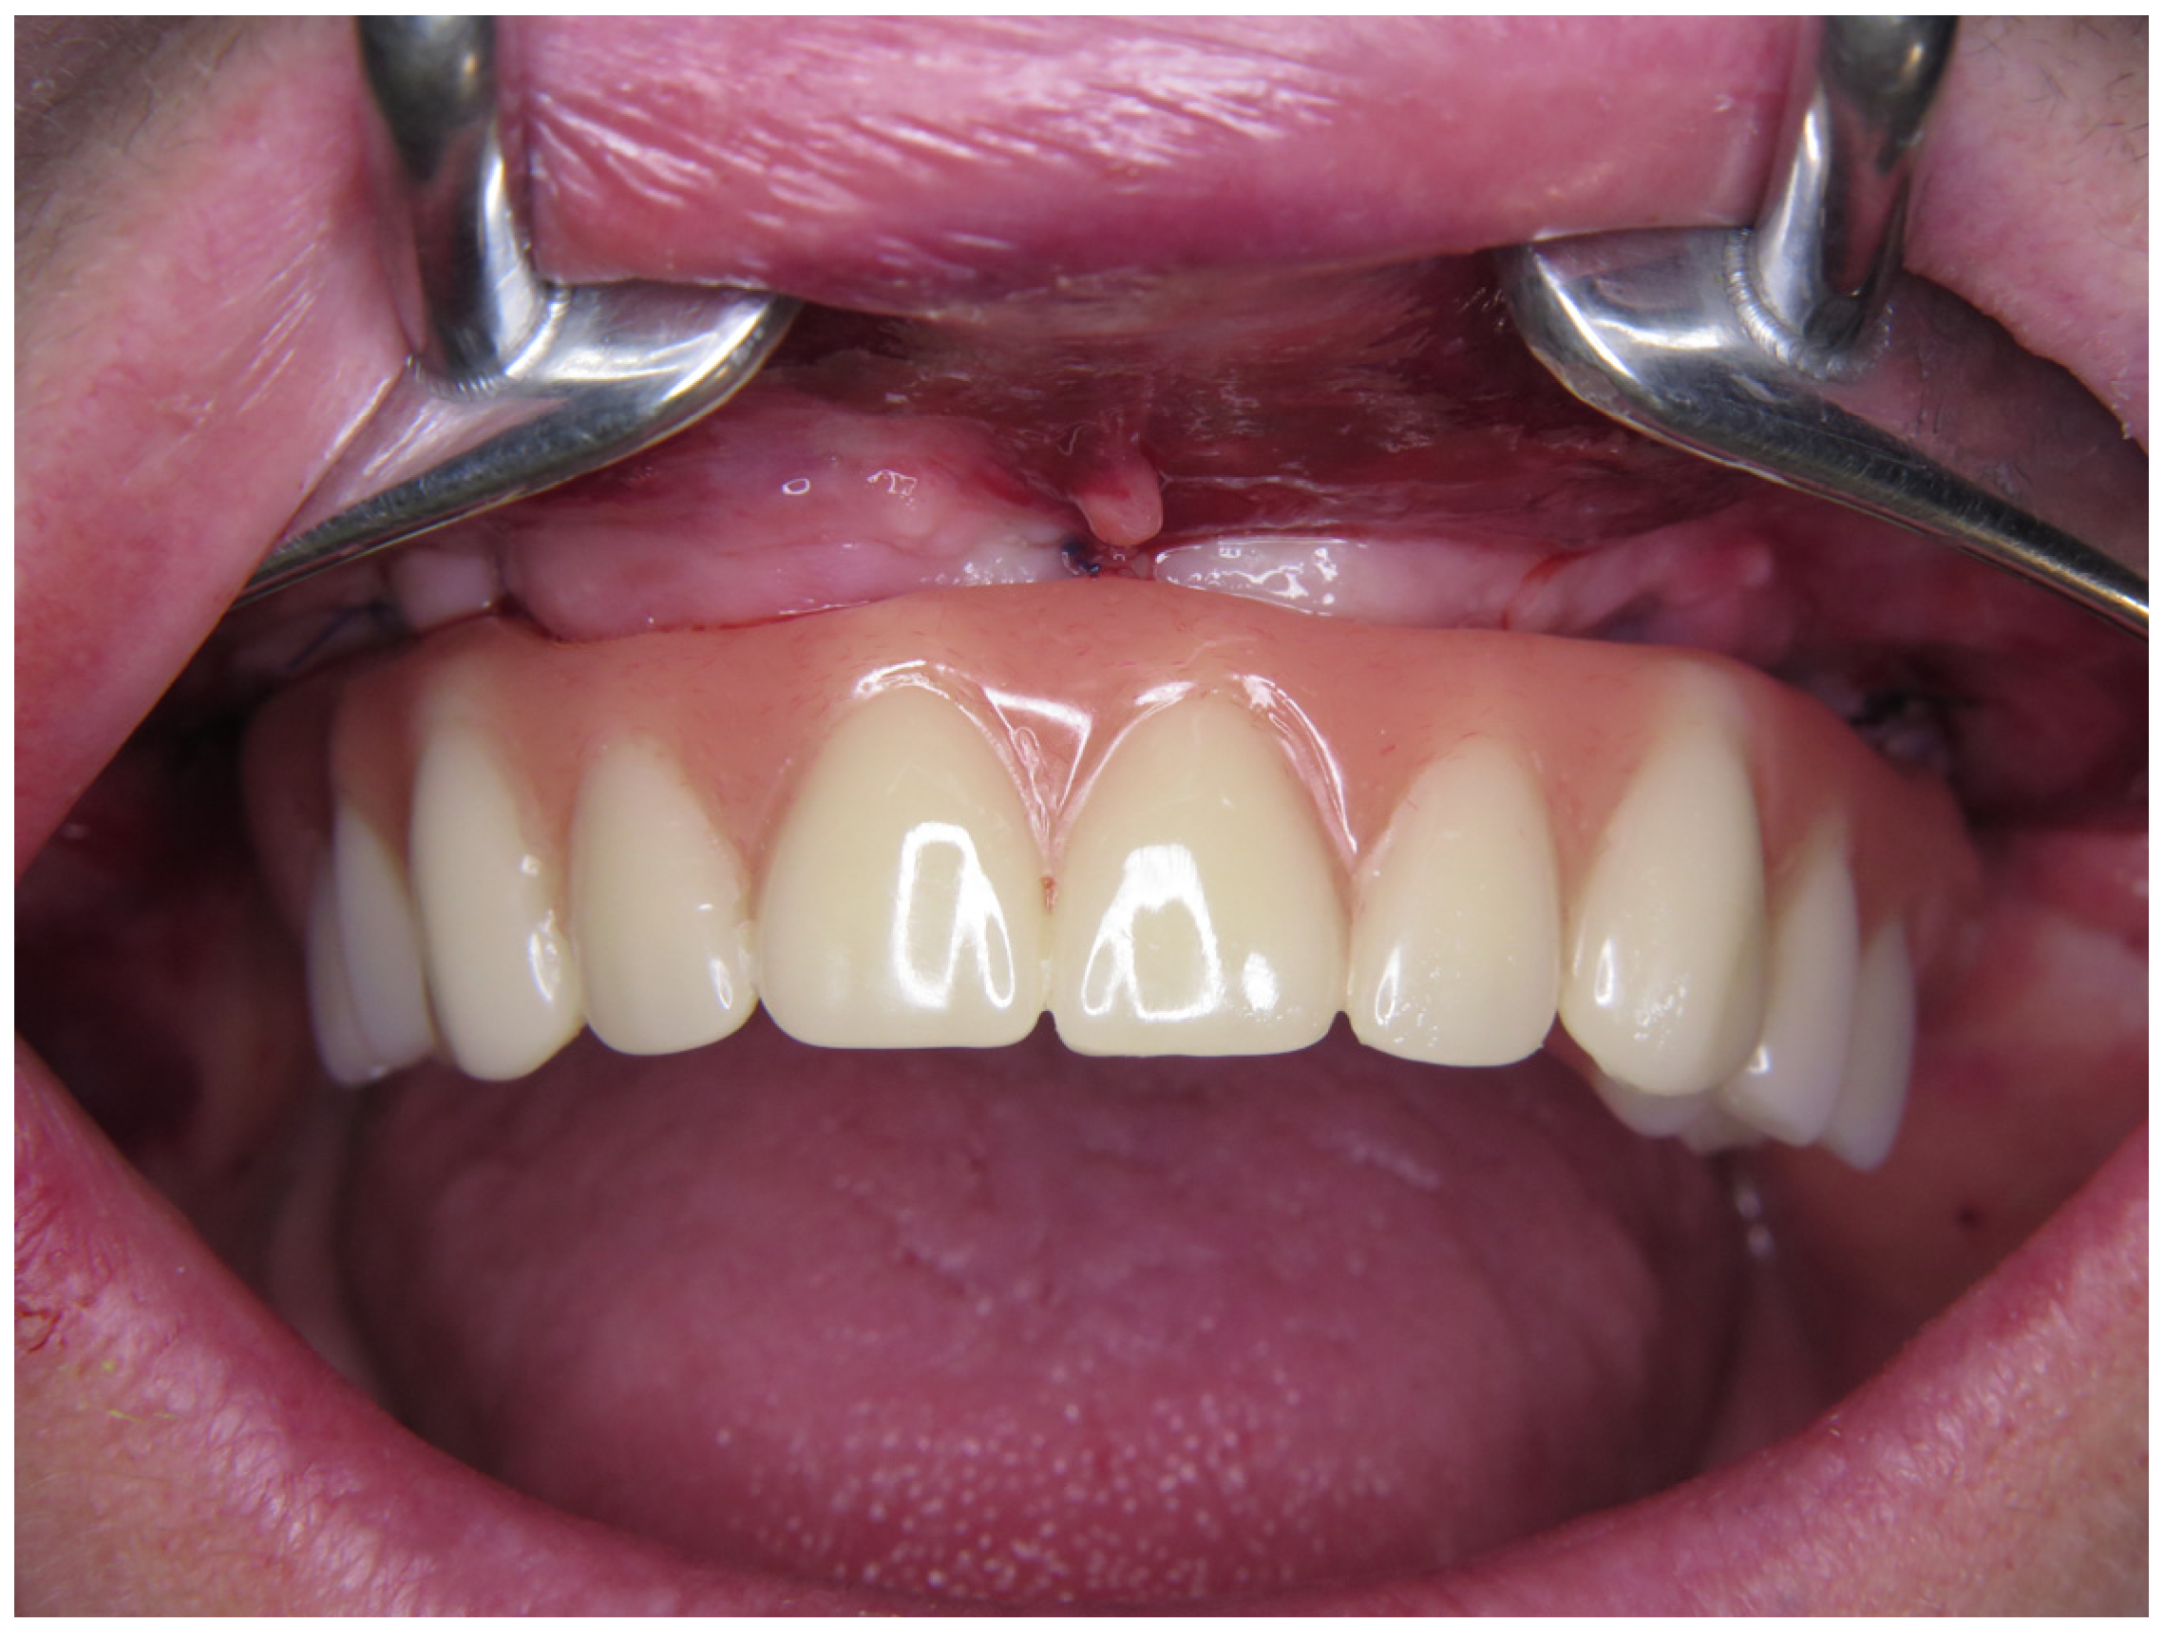

1. Introduction

2.4. Provisional Prosthetic Procedure

2.5. Final Prosthetic Procedure